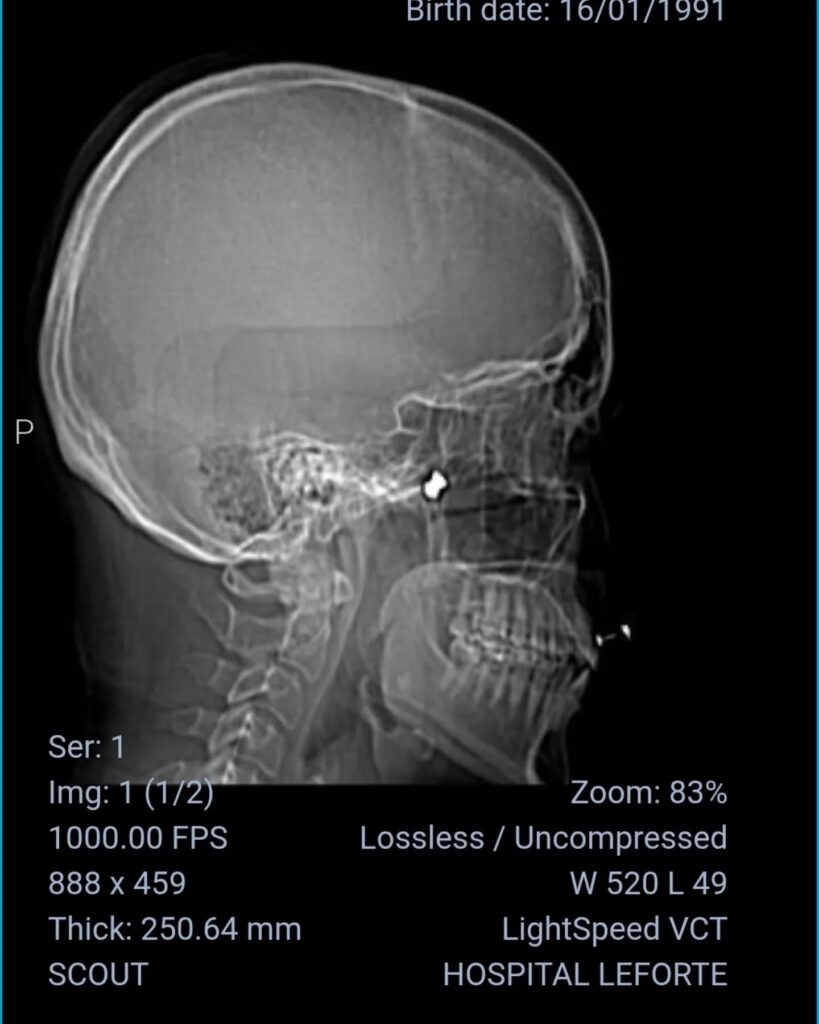

Um caso ficou conhecido recentemente: Irna Gambini, 28, moradora há anos do Jardim Anália Franco, no Tatuapé, sofreu um tiro de chumbinho que por pouco não lhe atingiu o olho esquerdo: “Eu tava num bar com meus amigos e por volta de meia noite, 1h da manhã, eu levei um tiro no rosto,só que eu achei que fosse uma pedrada. Pouco antes, um amigo sentiu algo lhe “beliscar” a perna, mas nós não pensamos na hora que se tratasse de um tiro. Quando dei por mim, vi o sangue escorrendo e entrei em pânico. Fui pro hospital e lá os médicos encontraram na tomografia a bala que estava alojada perto da órbita. Passei por cirurgia para retirada do projétil e por um milagre, eu não tive o olho estourado. Era para eu ter ficado cega desta vista”, afirma Irna.